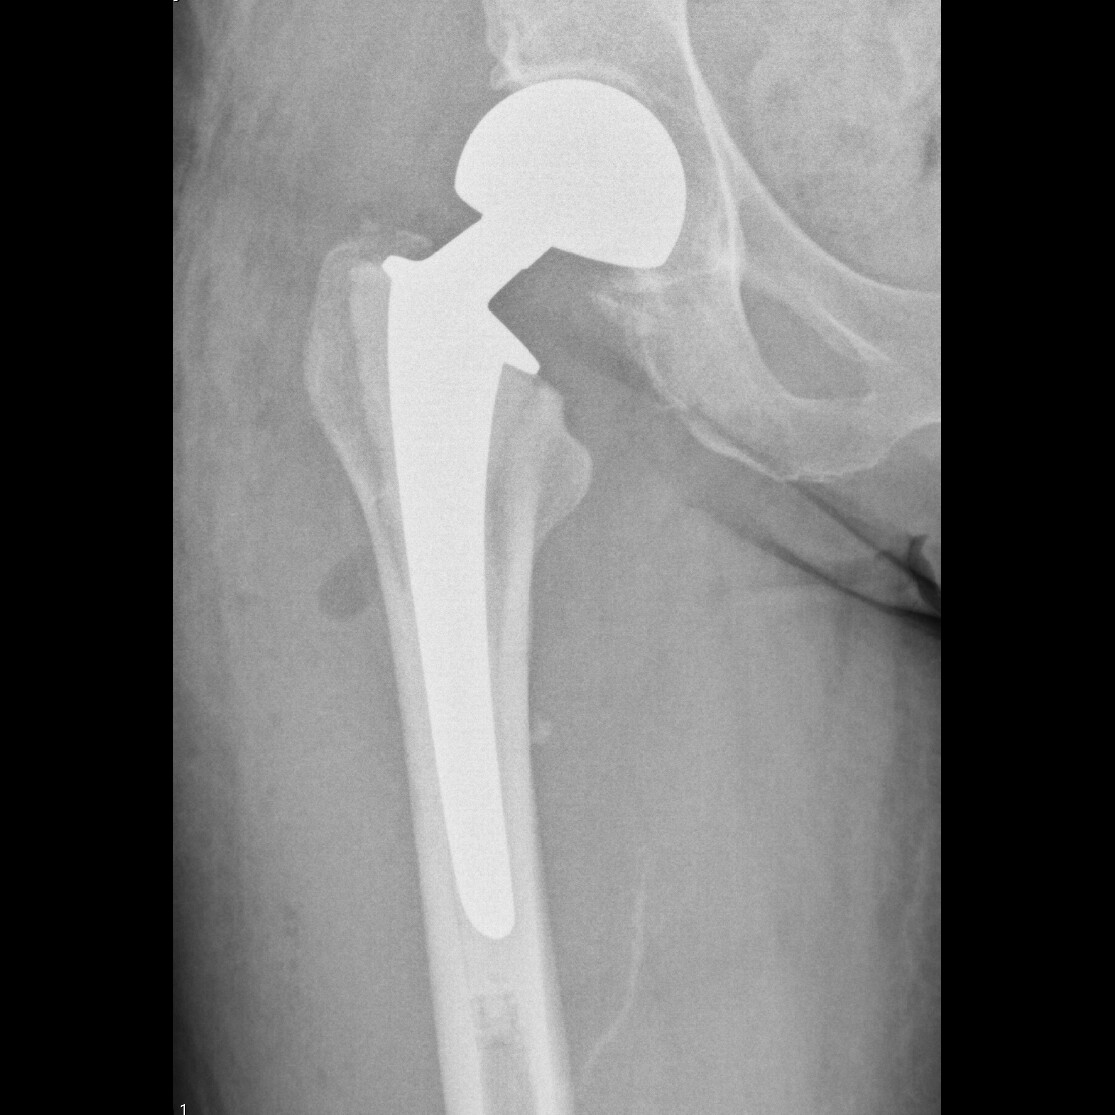

Total hip arthroplasty (in this case a uncemented stem with an uncemented cup)